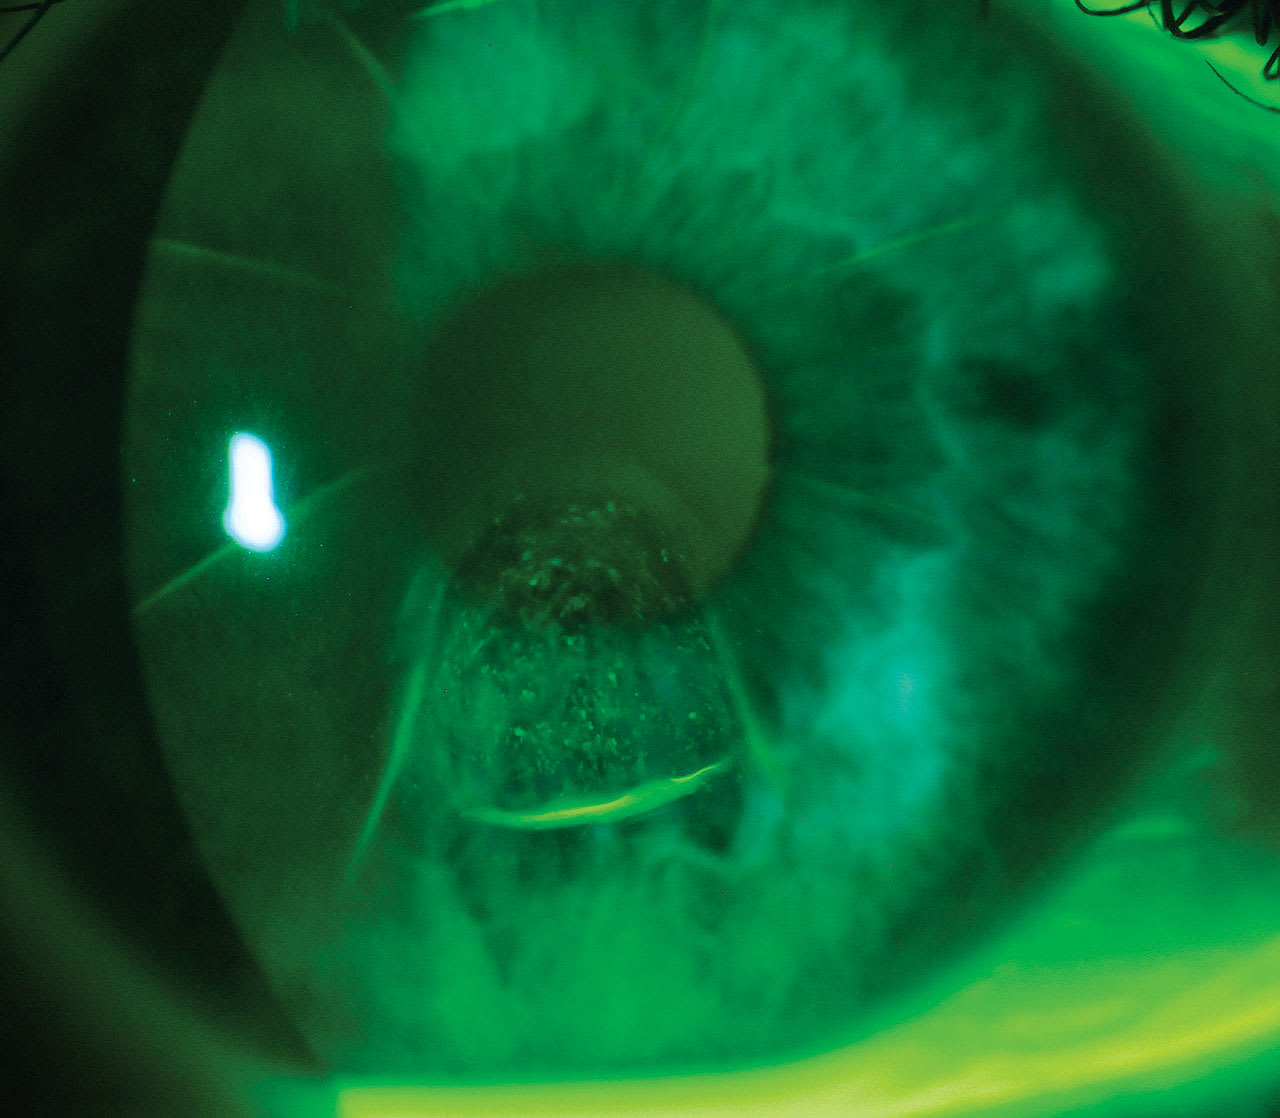

A 50-year-old female presented for a consultation for possible contact lens fitting. She had a history of radial keratotomy (RK) 20 years prior and had 15 years of good vision. Over the last five years, she reported decreasing vision. And over the last 12 months, she reported feeling unsafe driving and had taken a leave from her job as a nurse until she could improve her vision and become functional again. Best-spectacle-corrected vision was 20/60 in each eye. The slit lamp examination in the left eye looked similar to the right eye, pictured above.

The patient in the photo has corneal ectasia post radial and astigmatic keratotomy in both eyes. The area of ectasia is nestled between two radial cuts and an astigmatic cut. The area of staining correlates to the ectatic area, and the staining is comparable to swirl staining seen with keratoconus and GP lens wear, though this patient had not worn contact lenses. The swirl staining is likely a result of lid wiper pressure during normal blinking eroding the epithelium.

The patient was fitted in scleral lenses that fully vaulted the corneal surface. With the lenses, her visual acuity was 20/25 in each eye, 20/20 OU. The corneal surface and epithelial health improved with the lens wear, as the lens and the fluid reservoir protected the corneal surface from the focal rubbing by the lid wiper. She was able to return to driving and her job.